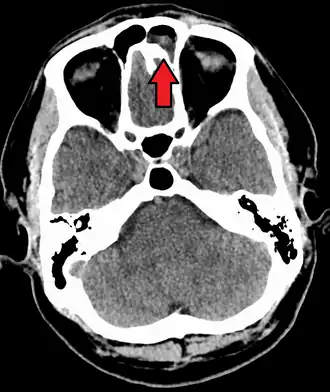

Intracranial complications

The proximity of the sinuses to the brain makes brain infections one of the most dangerous complications of acute bacterial sinusitis, especially when the frontal and sphenoid sinuses are involved. These infections can result from invasion of anaerobic bacteria through the bones or blood vessels. Abscesses, meningitis, and other life-threatening conditions may occur. In rare cases, mild personality changes, headache, altered consciousness, visual problems, seizures, coma, and even death may occur.[33]